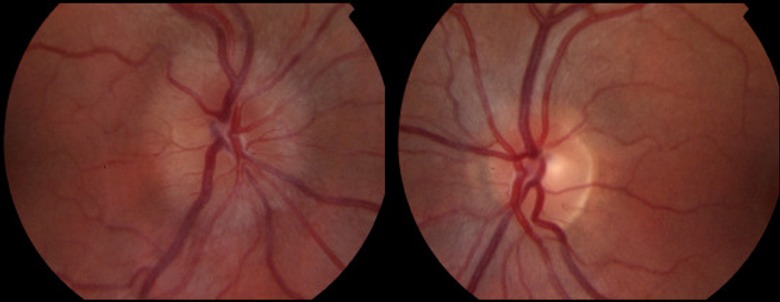

3. Sequential Fundus Photography

This imaging technique captures detailed images of the back of the eye, including the optic nerve, retina, and blood vessels, helping to document and monitor changes associated with neuro-ophthalmic conditions like papilledema, optic nerve drusen, and diabetic retinopathy.

AION (Arteritic Anterior Ischemic Optic Neuropathy) and NAION (Non-Arteritic Anterior Ischemic Optic Neuropathy) are conditions that affect the optic nerve, leading to sudden vision loss. They differ mainly in their underlying causes and treatments.

Swollen Optic Disc

An eye examination may reveal swelling of the optic disc, where the optic nerve enters the eye.